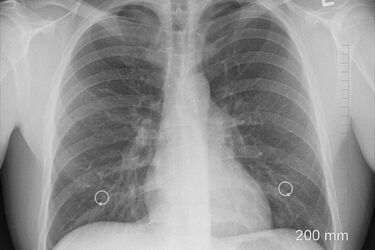

SP ZOZ w Łapach uruchomił nowe poradnie specjalistyczne. To poradnia gruźlicy i chorób płuc oraz poradnia urologiczna. Pacjenci już mogą się do nich rejestrować. W czwartek (1.07) jednostki mają ruszyć pełną parą. Poradnia gruźlicy i chorób płuc mieści się na parterze budynku głównego szpitala - w gabinecie nr A054 (przy windzie). Jest czynna w poniedziałki, środy i piątki w godz. 15:30-19:30. Z kolei poradnia urologiczna znajduje się na parterze budynku administracji (budynek D). Pacjenci mogą zgłaszać się we wtorki, środy, czwartki (godz. 15:30-19:30). Do obydwu poradni można rejestrować się telefonicznie 85 814 24 17. Przyjmowane są także osobiste zgłoszenia. Rejestracja poradni specjalistycznych mieści się w budynku głównym szpitala. - Rozwijamy szpital, chcemy aby z placówki o niezbyt dobrej sławie, stał się nowoczesną jednostką przyjazną pacjentom – mówi starosta białostostocki Jan Perkowski. W Szpitalu Powiatowym w Łapach działają już poradnie: chirurgiczna, urazowo-ortopedyczna, endokrynologiczna, kardiologiczna, dermatologiczna, nefrologiczna, neurologiczna, laryngologiczna, diabetologiczna, chorób wewnętrznych, pediatryczna, okulistyczna, ginekologiczno-położnicza, poradnia anestezjologiczna.